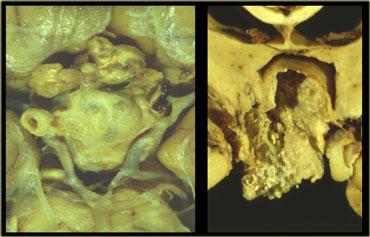

Sọ hầu u là bệnh lý thứ ba trong số ba bệnh lý có nguồn gốc từ biểu mô khe Rathke.

Về mặt kỹ thuật, đây là các khối u lành tính, nhưng khác với nang khe Rathke, chúng có thành dày và xâm lấn tại chỗ.

Về đại thể, đây là một khối phức tạp với nhiều nốt ở nền não, len lỏi dọc theo các khe não.

Thông thường, khối u không thể được cắt bỏ hoàn toàn.

Hình ảnh bên phải cho thấy một nang thành dày là một phần của sọ hầu u.